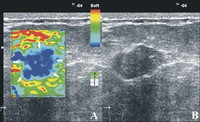

• Elastografie, die anhand der Verformbarkeit eines Knotens ein Bild erzeugt, mit dem man auf einen Tumor rückschließen kann